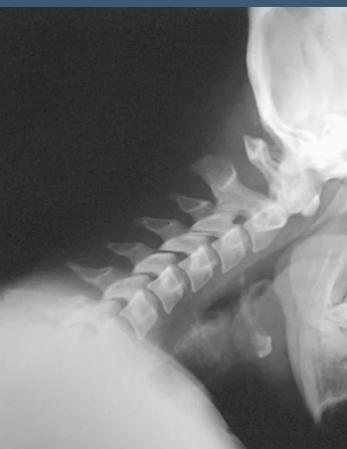

what view is this

hyperflexion

what is the point of seeing Lateral C-Spine Hyperflexion and Hyperextension

to show the range of motion, for anterioir posterioir motion

What is the patient position for lateral C-Spine hyperflexion?

Looking down to the floor (Have the patient put their chin as close to their chest as possible)